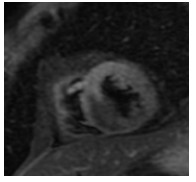

入院后签署患者知情同意告知书,查血常规、凝血谱、电解质、血生化、甲状腺功能、肿瘤标志物、C反应蛋白和脑钠肽均未见明显异常,心电图示窦性心律,顺钟向转位。连续心电遥控监护5 d未见明显室性心律失常。心脏超声和经食道心脏超声检查提示室间隔及左室下壁中段近后内侧乳头肌处可见一个偏高回声区,主要位于心肌内,浸润心肌全层,部分凸向左室腔,略见活动及变形,未累及二尖瓣和主动脉瓣,未见心腔流入道和流出道梗阻,未见明显心包积液。左心声学造影显示室间隔中下段偏强回声团块内未见明显血流信号,乏血供表现。心脏多层螺旋计算机断层扫描(CT)示室间隔内异常密度,测其CT值为-31.3 Hu,提示为脂肪组织密度,增强后病灶未见强化,诊断为脂肪来源肿瘤,脂肪瘤考虑(图 1~2)。心脏磁共振(CMRI)增强扫描示FIESTA序列显示后室间隔-左室下壁见一混杂高信号“小核桃”样大小肿物,T2WI(图 3)上为高信号,Triple IR序列(图 4)上病灶全部为低信号,提示为纯脂肪成分,病变周围可见低信号环,提示为化学位移伪影,病变质地较软,边界尚清楚,电影序列可见病灶柔软摆动,并随心动周期形态改变,局部突入左心室,舒张末期测量大小约25 mm×19 mm×36 mm,灌注序列见灌注确实,延迟增强未见强化,拟诊为心脏脂肪瘤(图 5)。SPECT心肌静息灌注显像见室间隔和左室下壁局部心肌血流灌注减低。18F-FDG PET-CT显像提示室间隔-左室下壁心肌内病变糖代谢减低,考虑为脂肪源性病变,全身未见局部异常密度增高。

| 图 4 心脏磁共振图(肿瘤在Triple IR序列上病灶全部为低信号,提示为纯脂肪成分) |